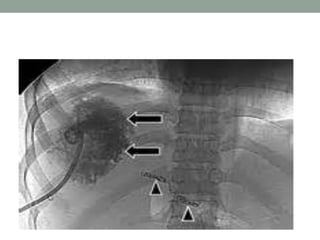

Imaging Studies

1. Chest X-Ray: May show raised right hemi-diaphragm on.

2. Ultrasonography

a) Can show abscess

b) Allow guided percutaneous aspiration and drainage and biliary

tree examination.

3. CT scanning

a) Can show the abscess,

b) Allow guided aspiration and drainage

c) Show other intra-abdominal abscesses or a possible cause

such as diverticular disease, appendicitis, etc.

d) Good for the detection of small abscesses.

4. MRI

Imaging

CXR Sono

CT SCAN